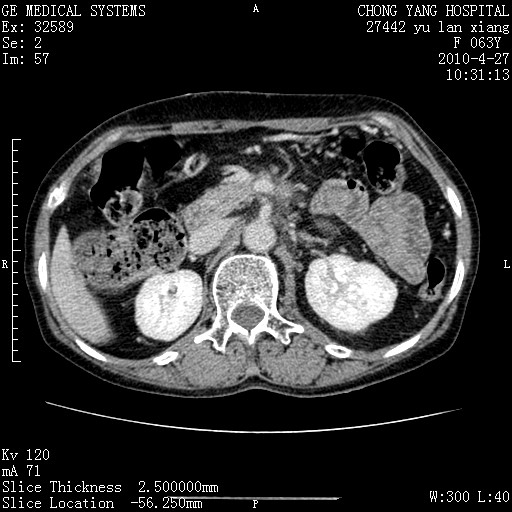

标题: CT26066:F63Y 上腹正中压痛半月,CA199:7400u/ml,MR示胰腺炎伴 [打印本页]

胰腺癌侵犯腹腔动脉干-分支、胃壁、左侧膈肌伴胰周及腹膜后淋巴结转移、胆囊切除术后。

胰腺癌侵犯腹腔动脉干-分支、胃壁、左侧膈肌伴胰周及腹膜后淋巴结转移、胆囊未显影。